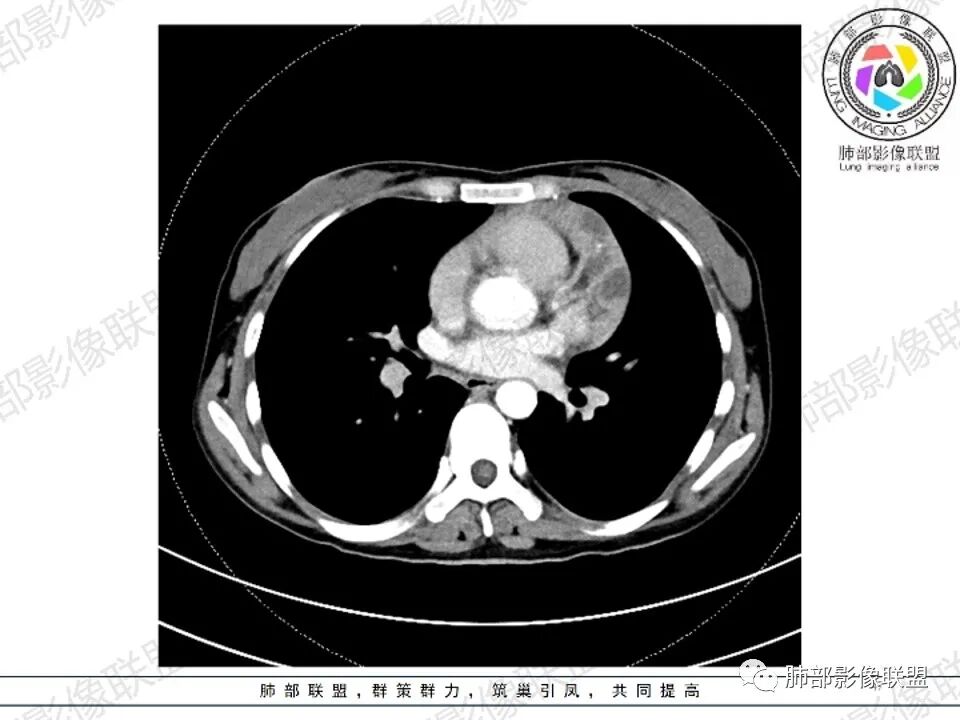

2.影像显示前纵隔不规则块状影,依势贴附心脏大血管旁,密度不均,边界不甚清楚,有结节融合感。

3.病灶轻度不均匀强化,可见血管穿行,散在液性低密度区。

双肺门未见肿大淋巴结。

4.双侧腋窝区见增大淋巴结,边界清楚。